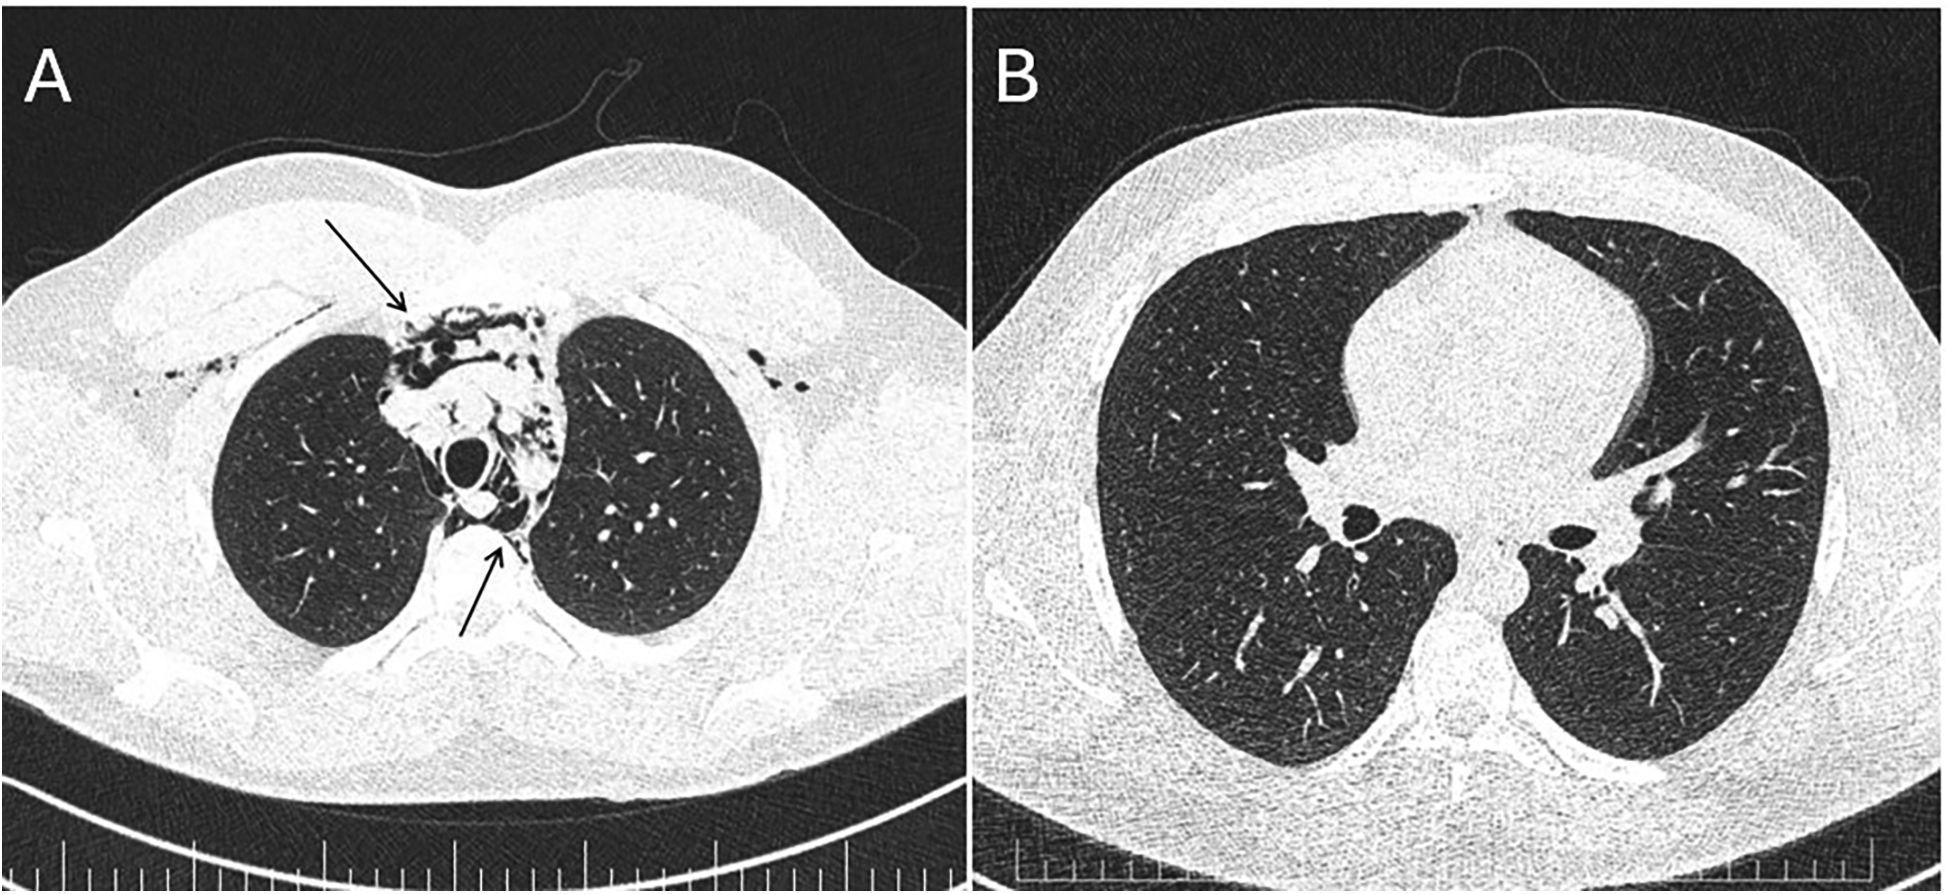

During acute coronary syndrome (ACS) exclusion workouts, transthoracic echocardiography images were very difficult to obtain, as hyperechoic moving artifacts were interfering with the ultrasound probe. Immediate chest x-ray showed massive pneumomediastinum (Figure 1). A subsequent CT scan confirmed the massive pneumomediastinum (Figure 2) and revealed the presence of an acute bilateral pulmonary embolism (Figure 3). Laboratory tests showed elevated D-Dimer levels (2,515 ng/mL), polycythaemia (hemoglobin 18.9 g/dL, haematocrit 55.5%), and slightly elevated creatinine (1.48 mg/dL, creatinine clearance 49 mL/min) with mild hypoalbuminemia (3.2 g/dL).

Figure 2

Panel (A) CT scan—massive pneumomediastinum—lung window demonstrating air in the anterior chest wall (upper arrow) and in the mediastinum (lower arrow). Panel (B) Repeat CT scan 7 days later—almost complete resolution of the pneumomediastinum.